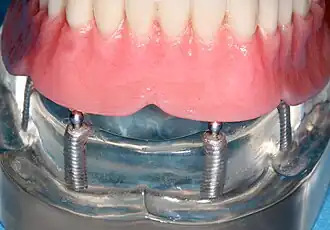

Four mandibular implants

Four lower implants to retain a complete denture with novaloc abutments

lower denture implant housing

Underside of a denture; housing fits like a ball and socket to hold the denture

When a removable denture is worn, retainers to hold the denture in place can be either custom made or "off-the-shelf" (stock) abutments. When custom retainers are used, four or more implant fixtures are placed and an impression of the implants is taken and a dental lab creates a custom metal bar with attachments to hold the denture in place. Significant retention can be created with multiple attachments and the use of semi-precision attachments (such as a small diameter pin that pushes through the denture and into the bar) which allows for little or no movement in the denture, but it remains removable.[30]: 33–34  However, the same four implants angled in such a way to distribute occlusal forces may be able to safely hold a fixed denture in place with comparable costs and number of procedures giving the denture wearer a fixed solution.[79]

Alternatively, stock abutments are used to retain dentures using a male-adapter attached to the implant and a female adapter in the denture. Two common types of adapters are the ball-and-socket style retainer and the button-style adapter. These types of stock abutments allow movement of the denture, but enough retention to improve the quality of life for denture wearers, compared to conventional dentures.[80] Regardless of the type of adapter, the female portion of the adapter that is housed in the denture will require periodic replacement, however the number and adapter type does not seem to affect patient satisfaction with the prosthetic for various removable alternatives.[81]